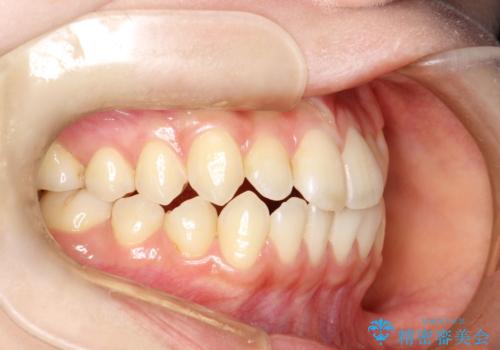

前歯のガタつき、下顎の前突感を治したい インビザライン矯正例

- 治療計画

- 学生時代に矯正治療を経験されていましたが、その後の後戻りによる前歯の叢生・下顎の前突感を主訴に来院されました。叢生や口元の突出感が軽度であった為、非抜歯にて側方拡大やIPRを組み込んでインビザラインにて治療を計画しました。前歯部にクロスバイトがあり、治療途中に上顎前歯が下顎前歯を乗り越えなければならない時期もありましたが、患者様の協力的なマウスピース装着もあり、良好な配列を達成しました。上下左右の親知らずは、当院にて矯正開始前に抜歯しました。